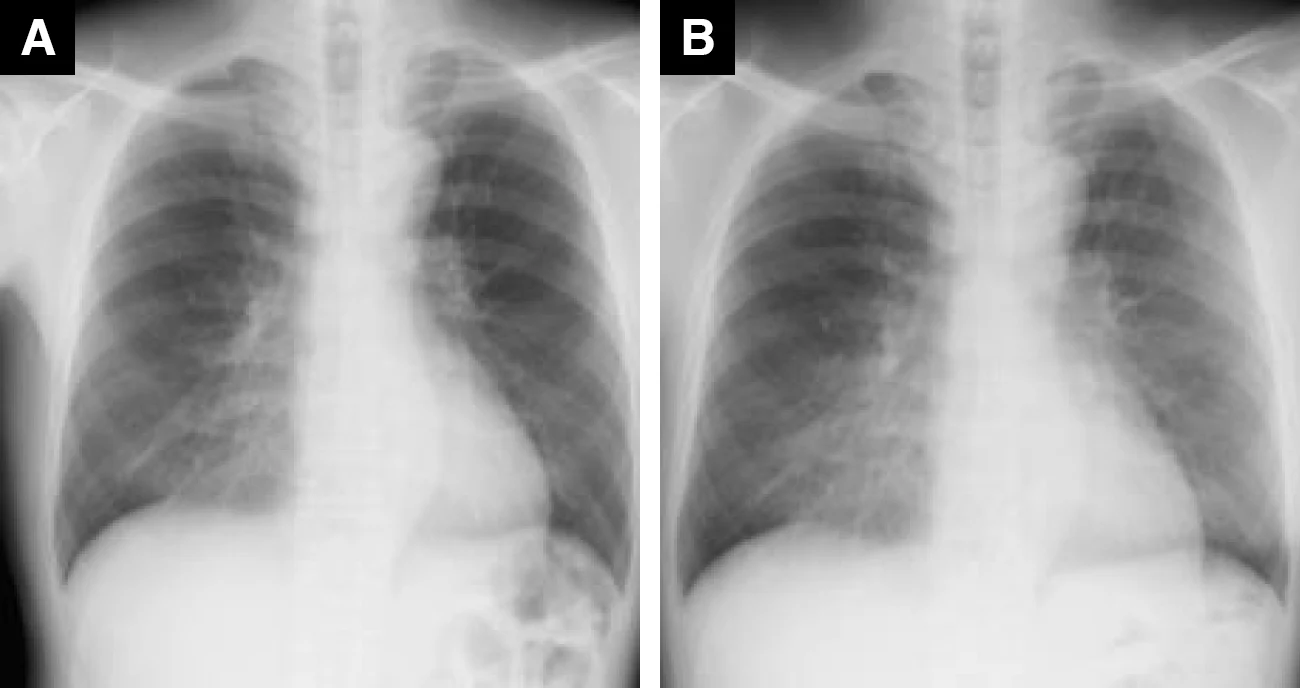

ドセタキセル投与症例(63歳、男性、乳がん)

A : 薬剤投与前 B : 薬剤投与後(紹介時)

Bでは極めて軽微ではあるが、両肺にすりガラス影を認めた

Bでは広範囲のすりガラス影がみられ、HP(過敏性肺炎)パターンと考えられた